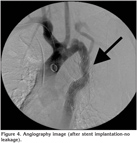

Surgical treatment can be considered as a treatment choice as well as intravascular stent implantation. In the HRCT of thorax and in the angiography, a blood leakage from graft to bronchial system can be seen. However, after the stent implantation, it's observed that the leakage completely stopped (Figure 3,4).

Figure 4